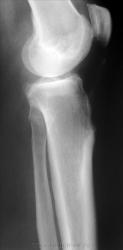

Или остеоид-остеома. Сделайте КТ

Тогда порекомендуйте аспириновый тест.